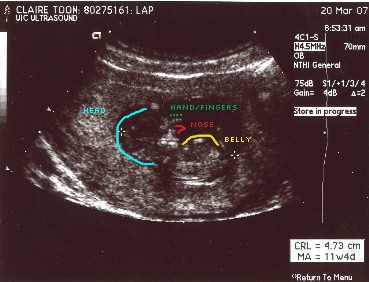

Here are the first pictures of Baby Zen. These ultrasound pictures were taken a few weeks ago at 12 weeks. I don't know about you, but sometimes the ultrasound pictures don't look like much of anything. I've included a guide picture to help you see Baby Zen. Just click on the pictures to make them larger.